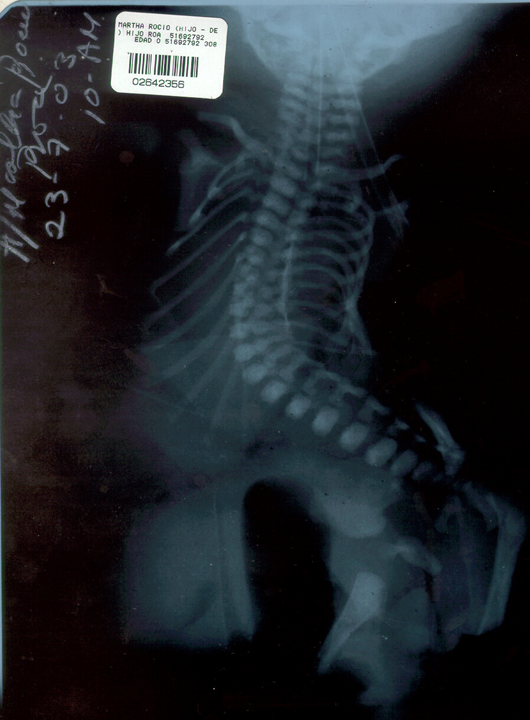

Male newborn, product of first gestation, preterm of a 39 year old mother and 42 year old father, both with blood group O, RH +. Mother with low prenatal controls, with positive results for IgG Toxoplasmosis and Rubeola, negative for HIV. After the born, peripheral blood karyotyping was performed, reporting 46 XY [20]. Normal male karyotype. (Figure 1) to discard chromosomal cause. Born by cesarean section, weight of 2,500 grams, height of 44 cm and head circumference of 35 cm. On physical examination, multiple malformations were observed such as microphthalmia, micrognathia, low-set ear lobes, short neck (Figure 1), bilateral equinus varus foot, short legs (Figure 2) and gastroschisis in the peritoneal bag showing the liver and intestinal segments (Figure 3). A spine x-ray was performed showing dorsal lumbar cyphoscoliosis, possible hip dysplasia, thorax with decreased anteroposterior diameter and pulmonary hypoplasia (Figure 4&5).

According to Van Allen, in 1987 he established the clinical manifestations that could be found taking into account that two of the following three must be present: a) exencephaly/encephalocele and/or facial clefts; b) thoraco and/or abdominoschisis and c) limb defects.3,6 There are also two phenotypic categories in which this complex can be classified as defined by Russo, being the cranioplacental, where craniofacial defects and/or upper limb defects can be observed; and the abdominal placental where defects are related to various degrees of thoracoabdominal evisceration, urogenital anomalies, imperforate anus, meningocele, severe spinal deformities, as resembled in our case by observing severe kyphoscoliosis (Figure 4) and involvement of lower extremities such as equinus varus foot (Figure 2). However, it is important to mention that there are cases in which the defects are variable and with different phenotype4,7 or internal anomalies are highly related (up to 95%)1 such as absence of diaphragm, intestinal atresia or cardiac defects.5